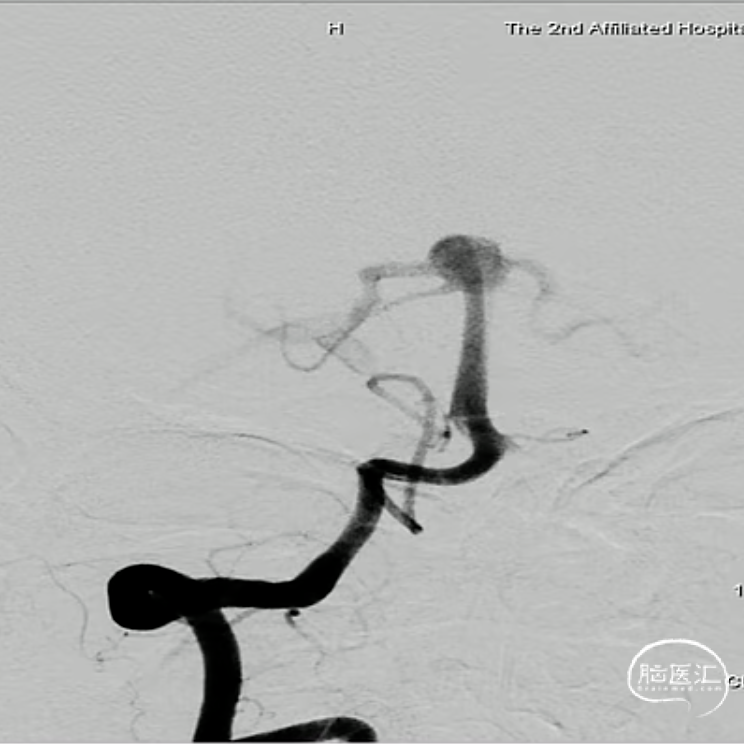

判断:基底动脉尖部动脉瘤WEB™术。

经测量可得动脉瘤宽度平均值为7.28mm,动脉瘤最小高度为4.91mm,参考尺寸选择表,选择WEB™ SL 8*4。

绝对瘤颈宽,右侧P1与瘤颈部分融合,容易疝出从而遮挡P1,应提前进行“分支保护”。

经VIA™微导管推送并释放WEB™ SL 8*4。

6个月后随访,Boss评分0级,动脉瘤完全闭塞不显影,WEB™完全栓塞。